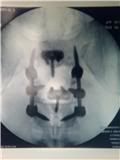

ok I saw my doc for the first time today since my surgery this is one of the pics he gave me.

I look like a flippin tsrget lol.

All titanium in me now I now where I can get broadheads if I run out now lmao